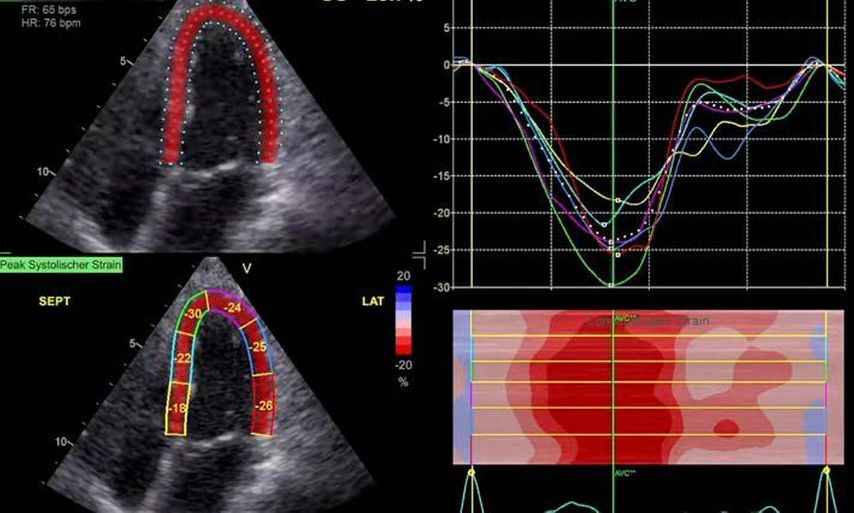

Im Echolabor des Pyhrn-Eisenwurzen Klinikums Steyr wird jede Form der Myokardwandverdickung mittels einer vollständigen Standardechokardiografie untersucht.2 Dabei wird auch ein Fokus auf die kontrastmittelunterstützte Sonografie gelegt, um die tatsächliche Dicke des Myokards zu vermessen.3 Die Verdickung sollte optimalerweise mittels 3D-LV-Massenmessung erfolgen. Die Messung im 2D-Bild ist dahingehend unterlegen. Ebenso wird jede Myokardwandverdickung mittels 2D-„strain imaging“ in der transthorakalen Echokardiografie (TTE) untersucht.4–6 Der „strain“ ist eine Messung der longitudinalen Funktion des Herzens (Video 1).

Der erste Fall beschäftigt sich mit einem Patienten mit einer hypertrophen Kardiomyopathie (HCMP). Er gibt eine deutliche Belastungsdyspnoe sowie einen ausgeprägten Leistungsknick an. Es wurde infolgedessen eine Untersuchung mittels standardisierter Echokardiografie inklusive „strain imaging“ durchgeführt. Der globale longitudinale „strain“ (GLS) mit –16% in Ruhe war gering reduziert. Es konnte kein relevanter LVOT-Gradient in Ruhe nachgewiesen werden. In der Belastungssituation (Handgrip, Valsalva, Kniebeugen und als Vorbereitung zur Untersuchung ein ausgiebiges Frühstück und Kaffee sowie ein am Vorabend konsumiertes Bier) konnte bei Kniebeugen mit einer Herzfrequenz von 126/min ein Spitzengradient bis 52mmHg dargestellt werden. Somit ergibt sich die Diagnose einer HOCMP mit einem belastungsinduzierten Gradienten. Bei bereits bestehender und ausgereizter Therapie unter Betablocker besteht die Indikation zur Therapie mittels des kardialen Myosininhibitors Mavacamten (Klasse-IIa-Empfehlung laut ESC).1 Darunter verbesserte sich die klinische Situation des Patienten deutlich, der Patient konnte uneingeschränkt Sport ausüben. Über die Zeit kam es zu einer geringen Reduktion der LV-Masse und einer geringen Zunahme des LV-„strain“. Die Belastungssituation zeigte durchwegs normale „strain“-Werte mit –20% (mit regionaler Reduktion bei Myokardwandverdickung im Sinne einer Hypertrophie). Die myokardiale Arbeit beim konkreten Patientenfall ist ebenso in Ruhe im grenzwertigen und unter Belastung im guten Normalbereich.6,8,9 Der Patient ist derzeit unter 5mg Mavacamten einmal täglich optimal eingestellt. Die EF in Ruhe ist konstant bei 50–55%. In Video 2 werden unterschiedliche Gradienten dargestellt, um eine HOCMP mit LVOTO von z.B. einer Mitralklappeninsuffizienz zu unterscheiden.Die Verdachtsdiagnose wurde mithilfe der Echokardiografie gestellt und durch das septal betonte „patchy“ LGE im MRT bestätigt.1,5

Die Paradedisziplin, die den „strain“ als Untersuchung in aller Munde gebracht hat, ist die Diagnostik der Amyloidose. Typisch (aber nicht pathognomonisch) ist dabei das „apical sparing“. In Video 3 ist ein Patient mit einer typischen ATTR-Amyloidose im „bullseye display“ des „strain“ im 17-Segmentmodell des LV zu sehen. Ebenso werden andere Zeichen in der Echokardiografie der Amyloidose präsentiert. Im konkreten Fall wurde die Sinnhaftigkeit, fast Notwendigkeit, der atrialen Bildgebung besprochen. Das Vollbild der Amyloidose zeigt eine deutliche Myokardwandverdickung des LV, in der frühen Phase kann diese jedoch noch fehlen. Als erstes Zeichen kann eine Veränderung des „strain“, insbesondere das linke Atrium (LA) betreffend, vorliegen.10 Somit ist in Summe festzuhalten, dass die Messung der longitudinalen Funktion des linken Atriums für eine Früherkennung erhöhter Füllungsdrücke dienlich sein kann, analog dem HbA1c für erhöhte Füllungsdrücke. Besonders bei einem LA-„strain“ in der Reservoirphase von unter 20% sollte man das Vorliegen einer möglichen beginnenden Form einer restriktiven Kardiomyopathie in Erwägung ziehen.1,10 Im MRT sind deutlich verlängerte T1-Zeiten ein Hinweis für das Vorliegen einer Amyloidose(neben dem generalisierten kreisrunden LGE (abhängig von der Aufzeichnungsphase und der Messung des erhöhten Extrazellulärvolumens).1

Andere Formen der Myokardwandverdickung, die mit „strain“ und MRT gut dargestellt werden können, sind einerseits die Differenzierung der Auswirkung der arteriellen Hypertonie (weiblich, 72a) bei Vorliegen einer Herzinsuffizienz mit normaler EF, einem GLS von –15,4%, einem LA-„strain“, in Reservoirphase 25% bei gering verlängerten T1-Zeiten im MRT. Andererseits kann Steroidabusus (männlich, 44a) zu einem reduzierten „strain“ mit gering verlängerten T1-Zeiten und einer Normalisierung der bildgebenden Befunde nach 2 Jahren nach Absetzen führen bzw. eine Mitochondriopathie (männlich, 32a) zu einer unklaren Myokardverdickung mit diffus reduziertem „strain“ und reduzierter LV-Funktion.4,11,12